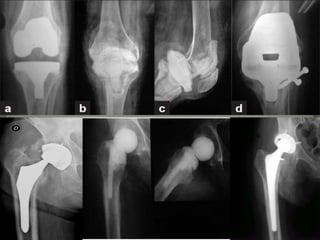

Prosthetic joint infections

• 1.

PRESENTED BY –Dr ANURAG RANA MODERATOR – Dr DEVENDRA CHOUHAN